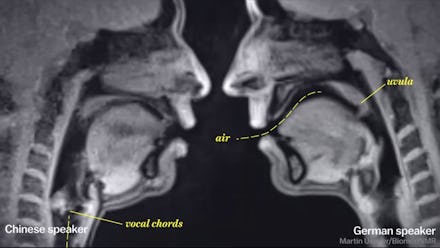

... or when we're talking different languages ...